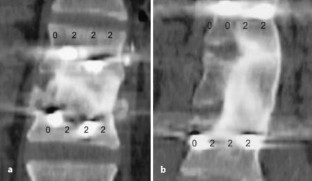

Bei 44 Patienten wurden standardisiert durchgeführte CT-Untersuchungen anonymisiert von 4 verschiedenen Untersuchern (Unfallchirurg, Orthopäde, 2 Radiologen) nach einem festgelegten Score ausgewertet. Der Score basiert auf der Beschreibung der Kontaktzonen zwischen Wirbelkörper und Knochenspan und ermöglicht eine Einteilung der Fusion in ausreichend, partiell und nicht ausreichend.

In a group of 44 patients a follow-up CT scan was evaluated with a standardized scoring system by four different independent evaluators (a trauma surgeon, an orthopedic surgeon, and two radiologists). The score is based on the morphologic classification of the region between graft and vertebral body. It allows a classification of the spondylodesis as sufficient, partial, and not sufficient.